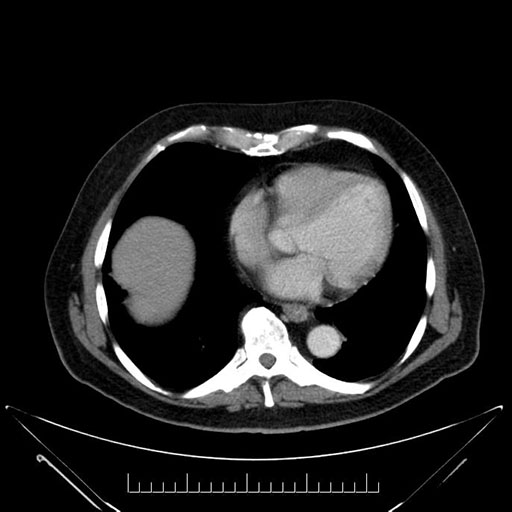

Axial - 3 months prior